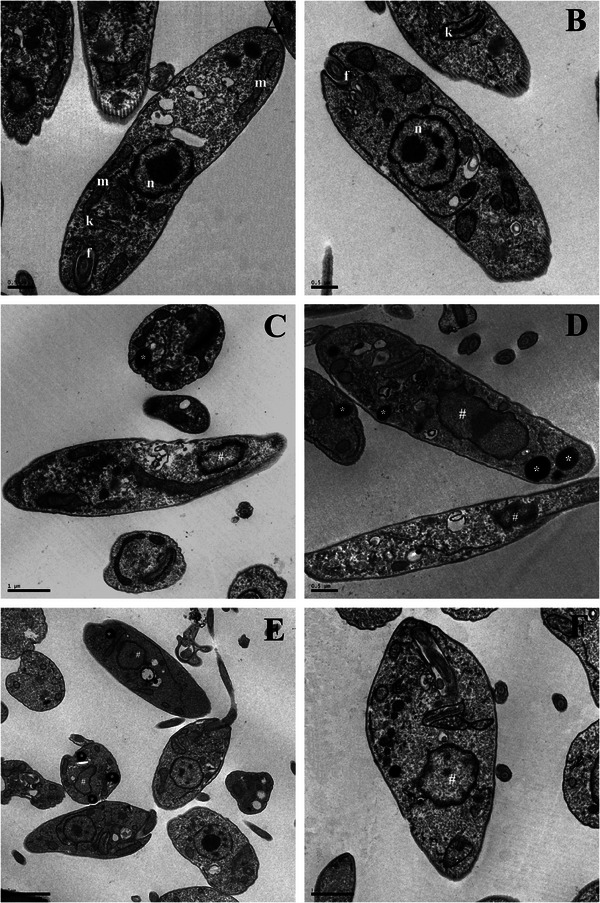

Additionally, transmission electron microscopy (TEM) revealed ultrastructural alterations in L. infantum promastigotes treated with HE (Figure 3C,D) and 4‐NC (1) (Figure 3E,F), including nuclear DNA disorganization and mitochondrial damage. In contrast, untreated control parasites (Figure 3A,B) displayed normal ultrastructure without any observable alterations.

On the basis of these ultrastructural findings, further spectrophotometric assays were conducted to investigate the mechanism of action of HE and 4‐NC (1) against L. infantum promastigotes. The images showed alterations in the Leishmania mitochondria. On the basis of this, we decided to evaluate the ΔΨ m in treated parasites. A marked decrease in Rh123 fluorescence intensity was observed, indicating mitochondrial depolarization in both treatments (Figure 4A–C).